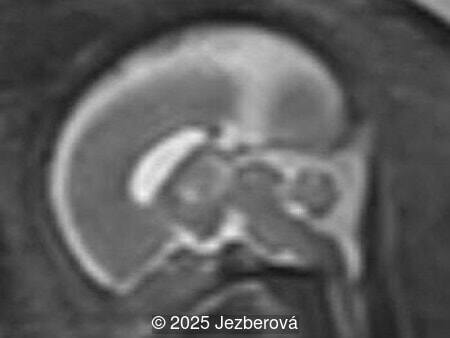

We present a case of agenesis of the cavum septum pellucidum (CSP).

At 20 weeks, detailed ultrasound under conditions of severe oligohydramnios demonstrated absence of the typical box-shaped anechoic structure of the cavum septum pellucidum (CSP). The frontal horns of the lateral ventricles appeared narrow and pointed, giving the characteristic “bull’s horns sign.” Multiplanar and 3D reconstructions confirmed the presence of the corpus callosum, while the CSP was absent. Other midline and posterior fossa structures appeared normal. The optic chiasm was partially visualized, although assessment was limited by technical conditions. Fetal magnetic resonance imaging (MRI) was subsequently performed and confirmed isolated agenesis of the CSP with preserved corpus callosum and posterior fossa structures. The optic chiasm and pituitary stalk are visible in the sellar region, but the pituitary gland itself is not clearly identified in the sella turcica as it is a very small structure. No additional central nervous system anomalies were detected.